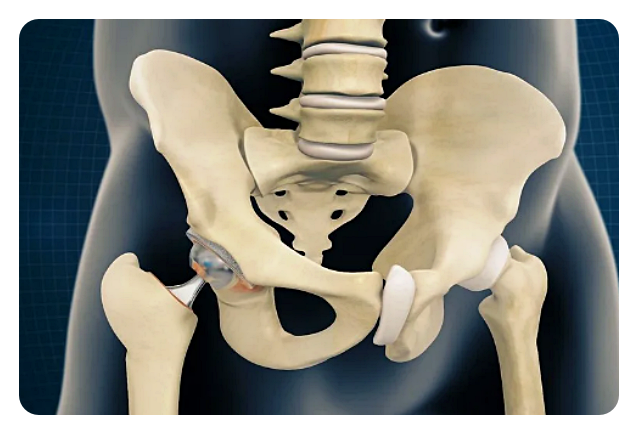

고관절은 몸을 지탱하고 움직이는 데 중요한 역할을 하는데, 골반과 대퇴골을 연결하는 관절입니다. 우리의 일상적인 활동에서도 이 관절은 걷기나 뛰기와 같은 움직임뿐만 아니라 체중을 지탱하고 다리를 움직이는 데에 필수적입니다. 그러나 나이가 들거나 부상 등으로 고관절이 손상되면 통증과 움직임 제한과 같은 문제가 발생할 수 있습니다.

인공관절 치환술: 이 수술은 고관절이 심각하게 손상되거나 통증으로 인해 일상 생활에 지장을 주는 경우에 시행됩니다. 이 수술은 손상된 관절을 제거하고 인공 관절로 대체함으로써 이루어집니다.